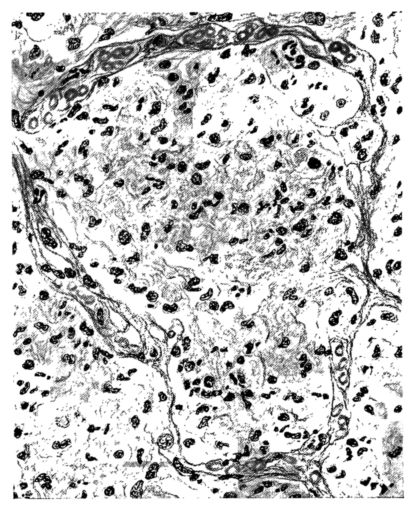

FIG. IV. AUTOPSY NO. 205. CONGESTION AND EDEMA OF THE SUBMUCOSA AND REGENERATION OF THE TRACHEAL EPITHELIUM.

The changes are less marked, perhaps, in the trachea than in its finer ramifications. The mucosa is constantly more or less destroyed and large areas, usually focal, are entirely devoid of their epithelial covering. This is replaced by a sparse exudate, composed largely of red blood cells, mucus, a small amount of fibrin, and nuclear fragments (Fig. II). It may dip into the submucosa for a short distance, but usually these indentures are associated with the ducts of the mucous glands into which the inflammatory reaction extends. A more striking feature than the exudate, however, is the edema and the congestion of the submucosa. The loose areolar tissue of the submucosa is spread widely apart, and throughout it distended blood vessels are very conspicuous. Occasionally such a vessel is broken and actual hemorrhage appears in the submucosa. Occasionally, too, the inflammation extends down the duct to the mucous gland itself, and here, also, aplastic inflammatory reaction is evident, inasmuch as the acini now stain intensely red with the cells undifferentiated from each other and specked here and there by broken remains of the dead nuclei (Fig. III). After the disease has continued for a short period, even at the end of five or six days, some regeneration of the epithelial lining may be seen (3) (Fig. IV). But despite this, the acute picture persists, and there goes on, side by side, an attempted repair characterized by epithelial regeneration and the same evidence of acute change. Since the lesion is essentially a superficial one, scars or contractures of any extent are not encountered in the trachea, even in examples of the disease that have ended fatally only after many weeks.[4]